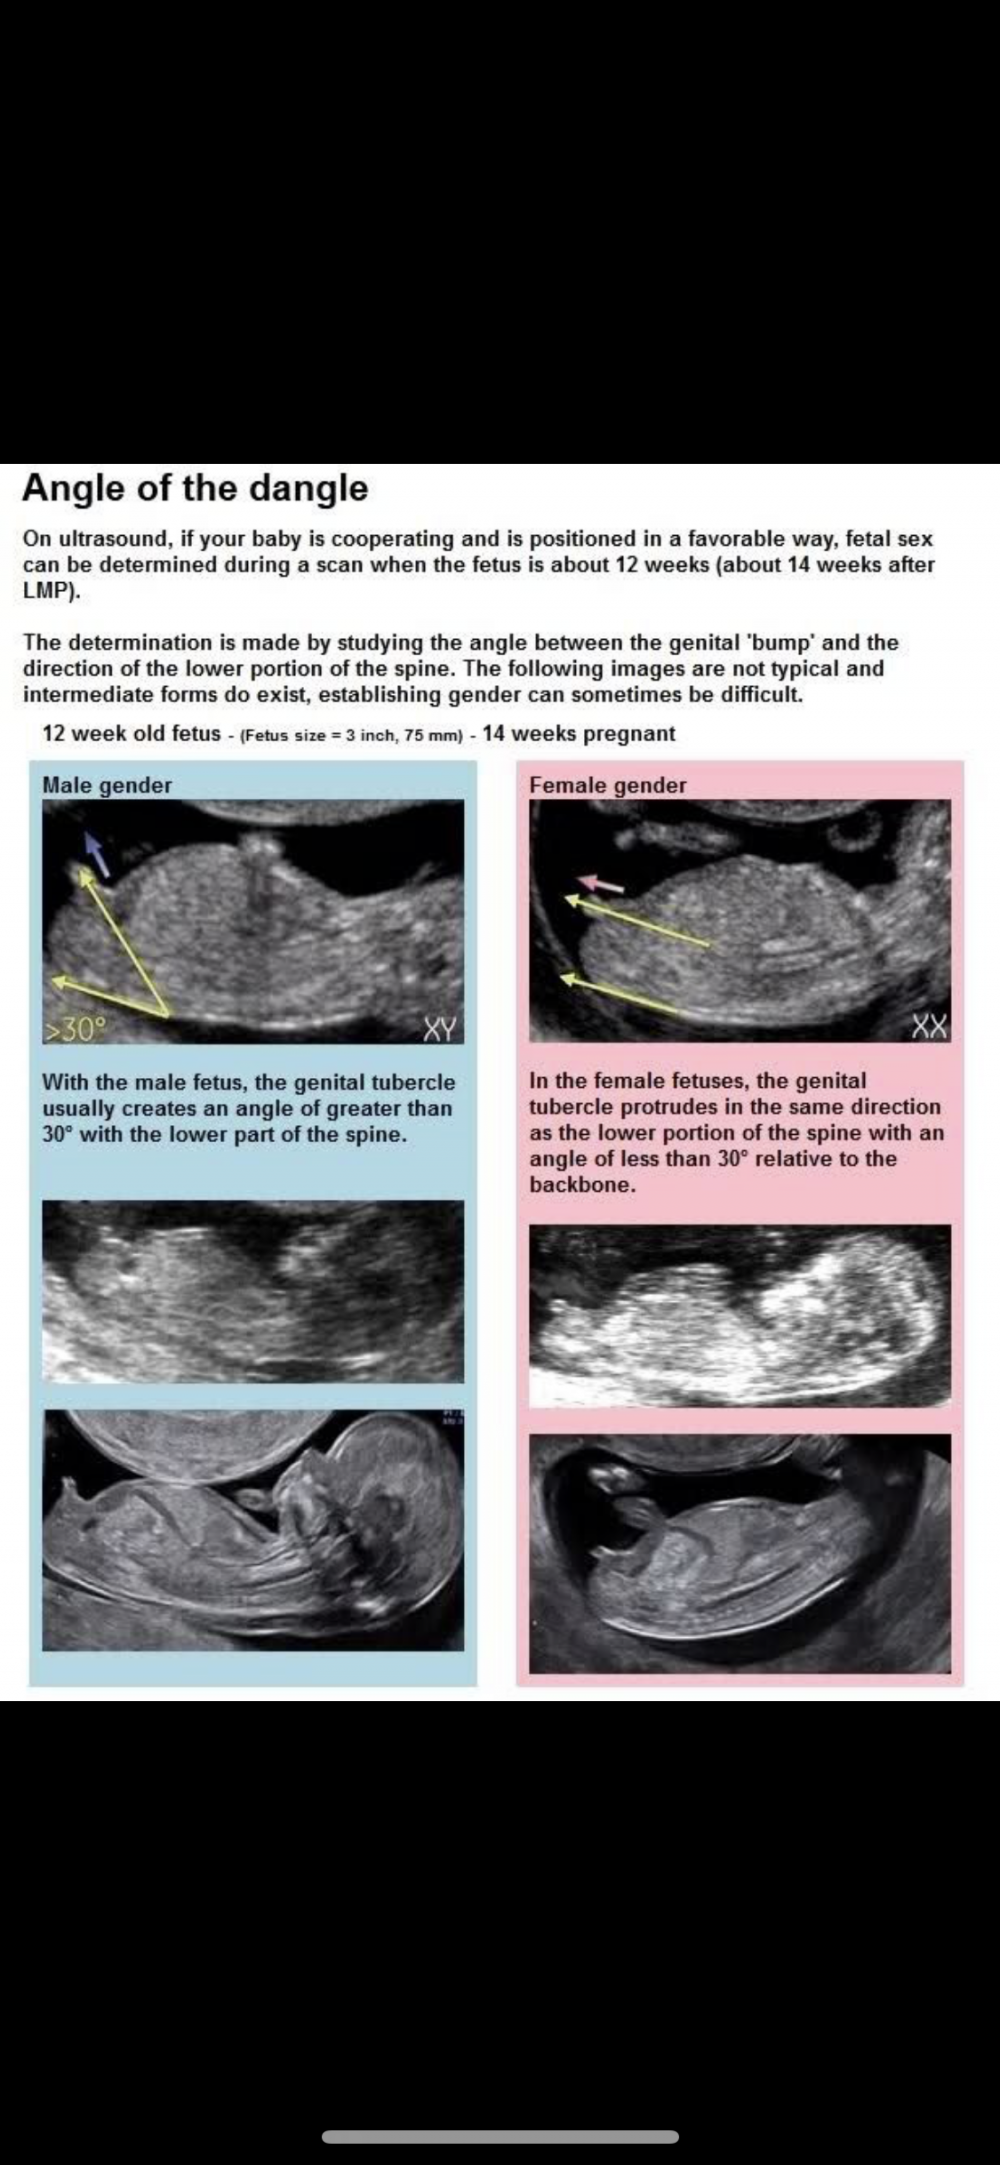

بنات هذي نظريه طبقوها على سوناراتكم من الاسبوع ١٢.. او ١١ او ١٣ نبغا نشوف صحتها😍 انا نسيت صور السونار حقي سويته في الاسبوع ١٣ بس ما اخذتها من الاستقبال وبروح اليوم استلمها ان شاء الله يعطوني